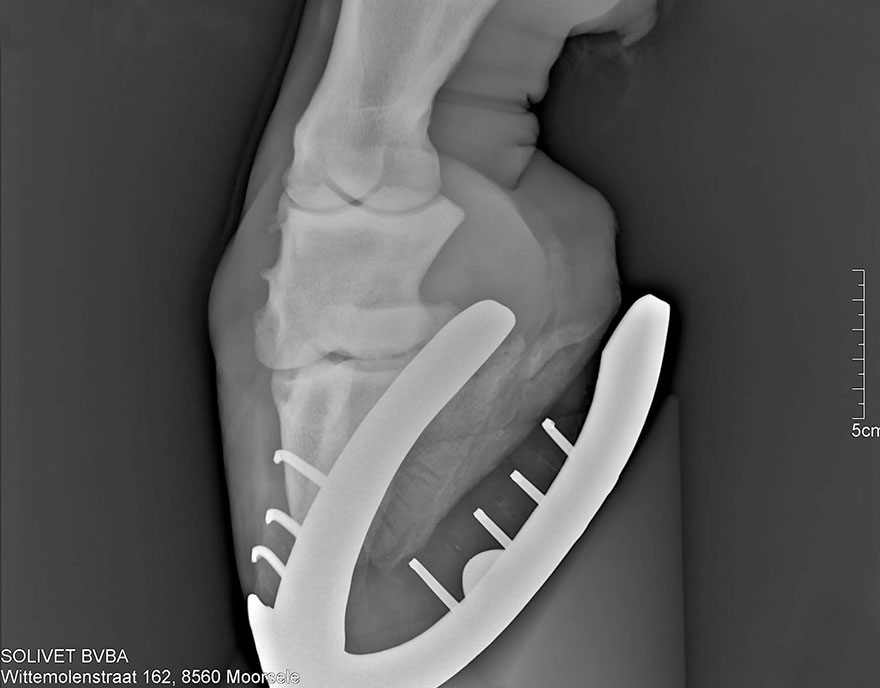

Radiografische keuring

Een radiografische keuring houdt in dat we RX beelden maken van de gewrichten van het paard om degeneratieve aandoeningen (bv. artrose, hoefkatrol) of fragmenten (OCD) in de gewrichten vast te stellen. Op die manier proberen we u een zo volledig mogelijk beeld van uw paard te geven zodat u goed geïnformeerd bent alvorens tot de koop van het paard over te gaan.

Radiografie

Aan de hand van ons draadloos radiografie toestel is het mogelijk om bij u thuis RX-beelden te maken. De beelden komen direct op een computerscherm zodat ze direct beoordeeld kunnen worden. RX- beelden kunnen gemaakt worden in het kader van een aankooponderzoek, kreupelheid of tandproblemen.